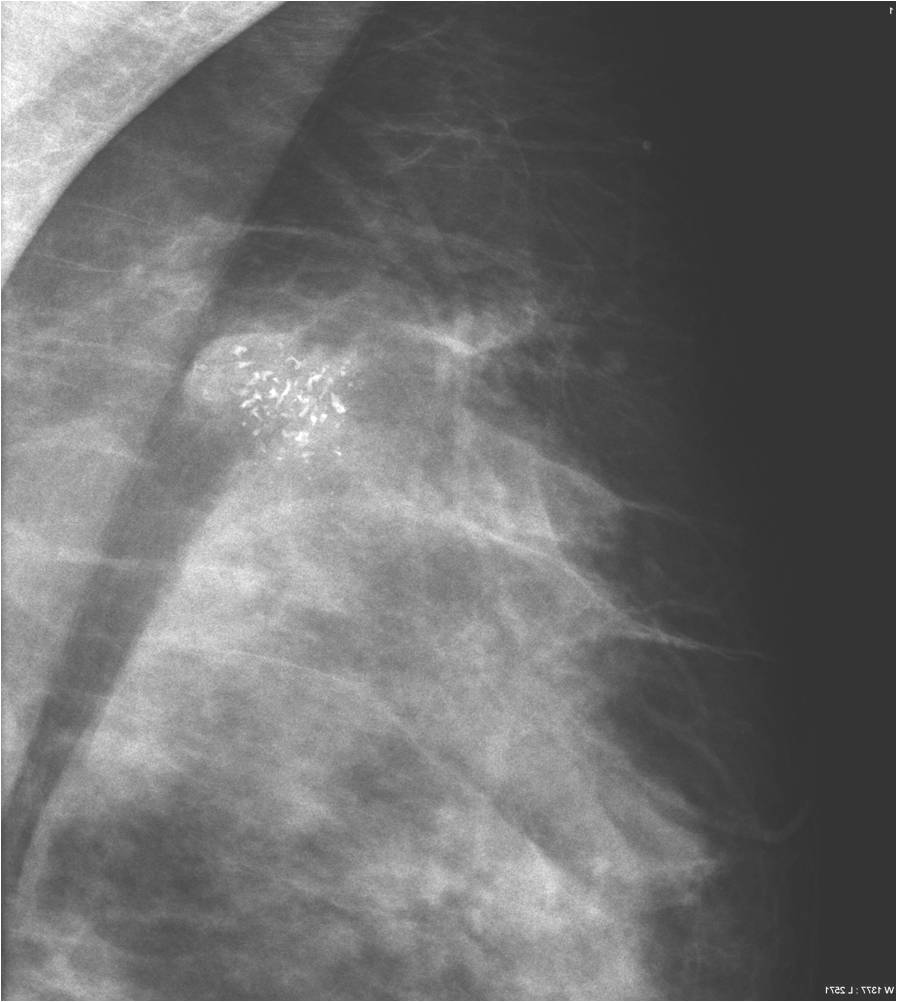

Calcifications are encountered in the breast quite often. Most of them accompany benign process (Picture 21.) and only a smaller percentage actually indicates malignancy. These malignant signs are basically always micro-calcifications. They are ill-shaped, with various pleomorphism (Pictures 23.,24.) and they are usually show a clustered arrangement. Their number is irrelevant to the grade of malignancy. Their analysis with mammography is often hard, but targeted and magnified images can help in it. In most the cases these lesion can’t be identified with ultrasound, so stereotaxy core biopsy is needed.